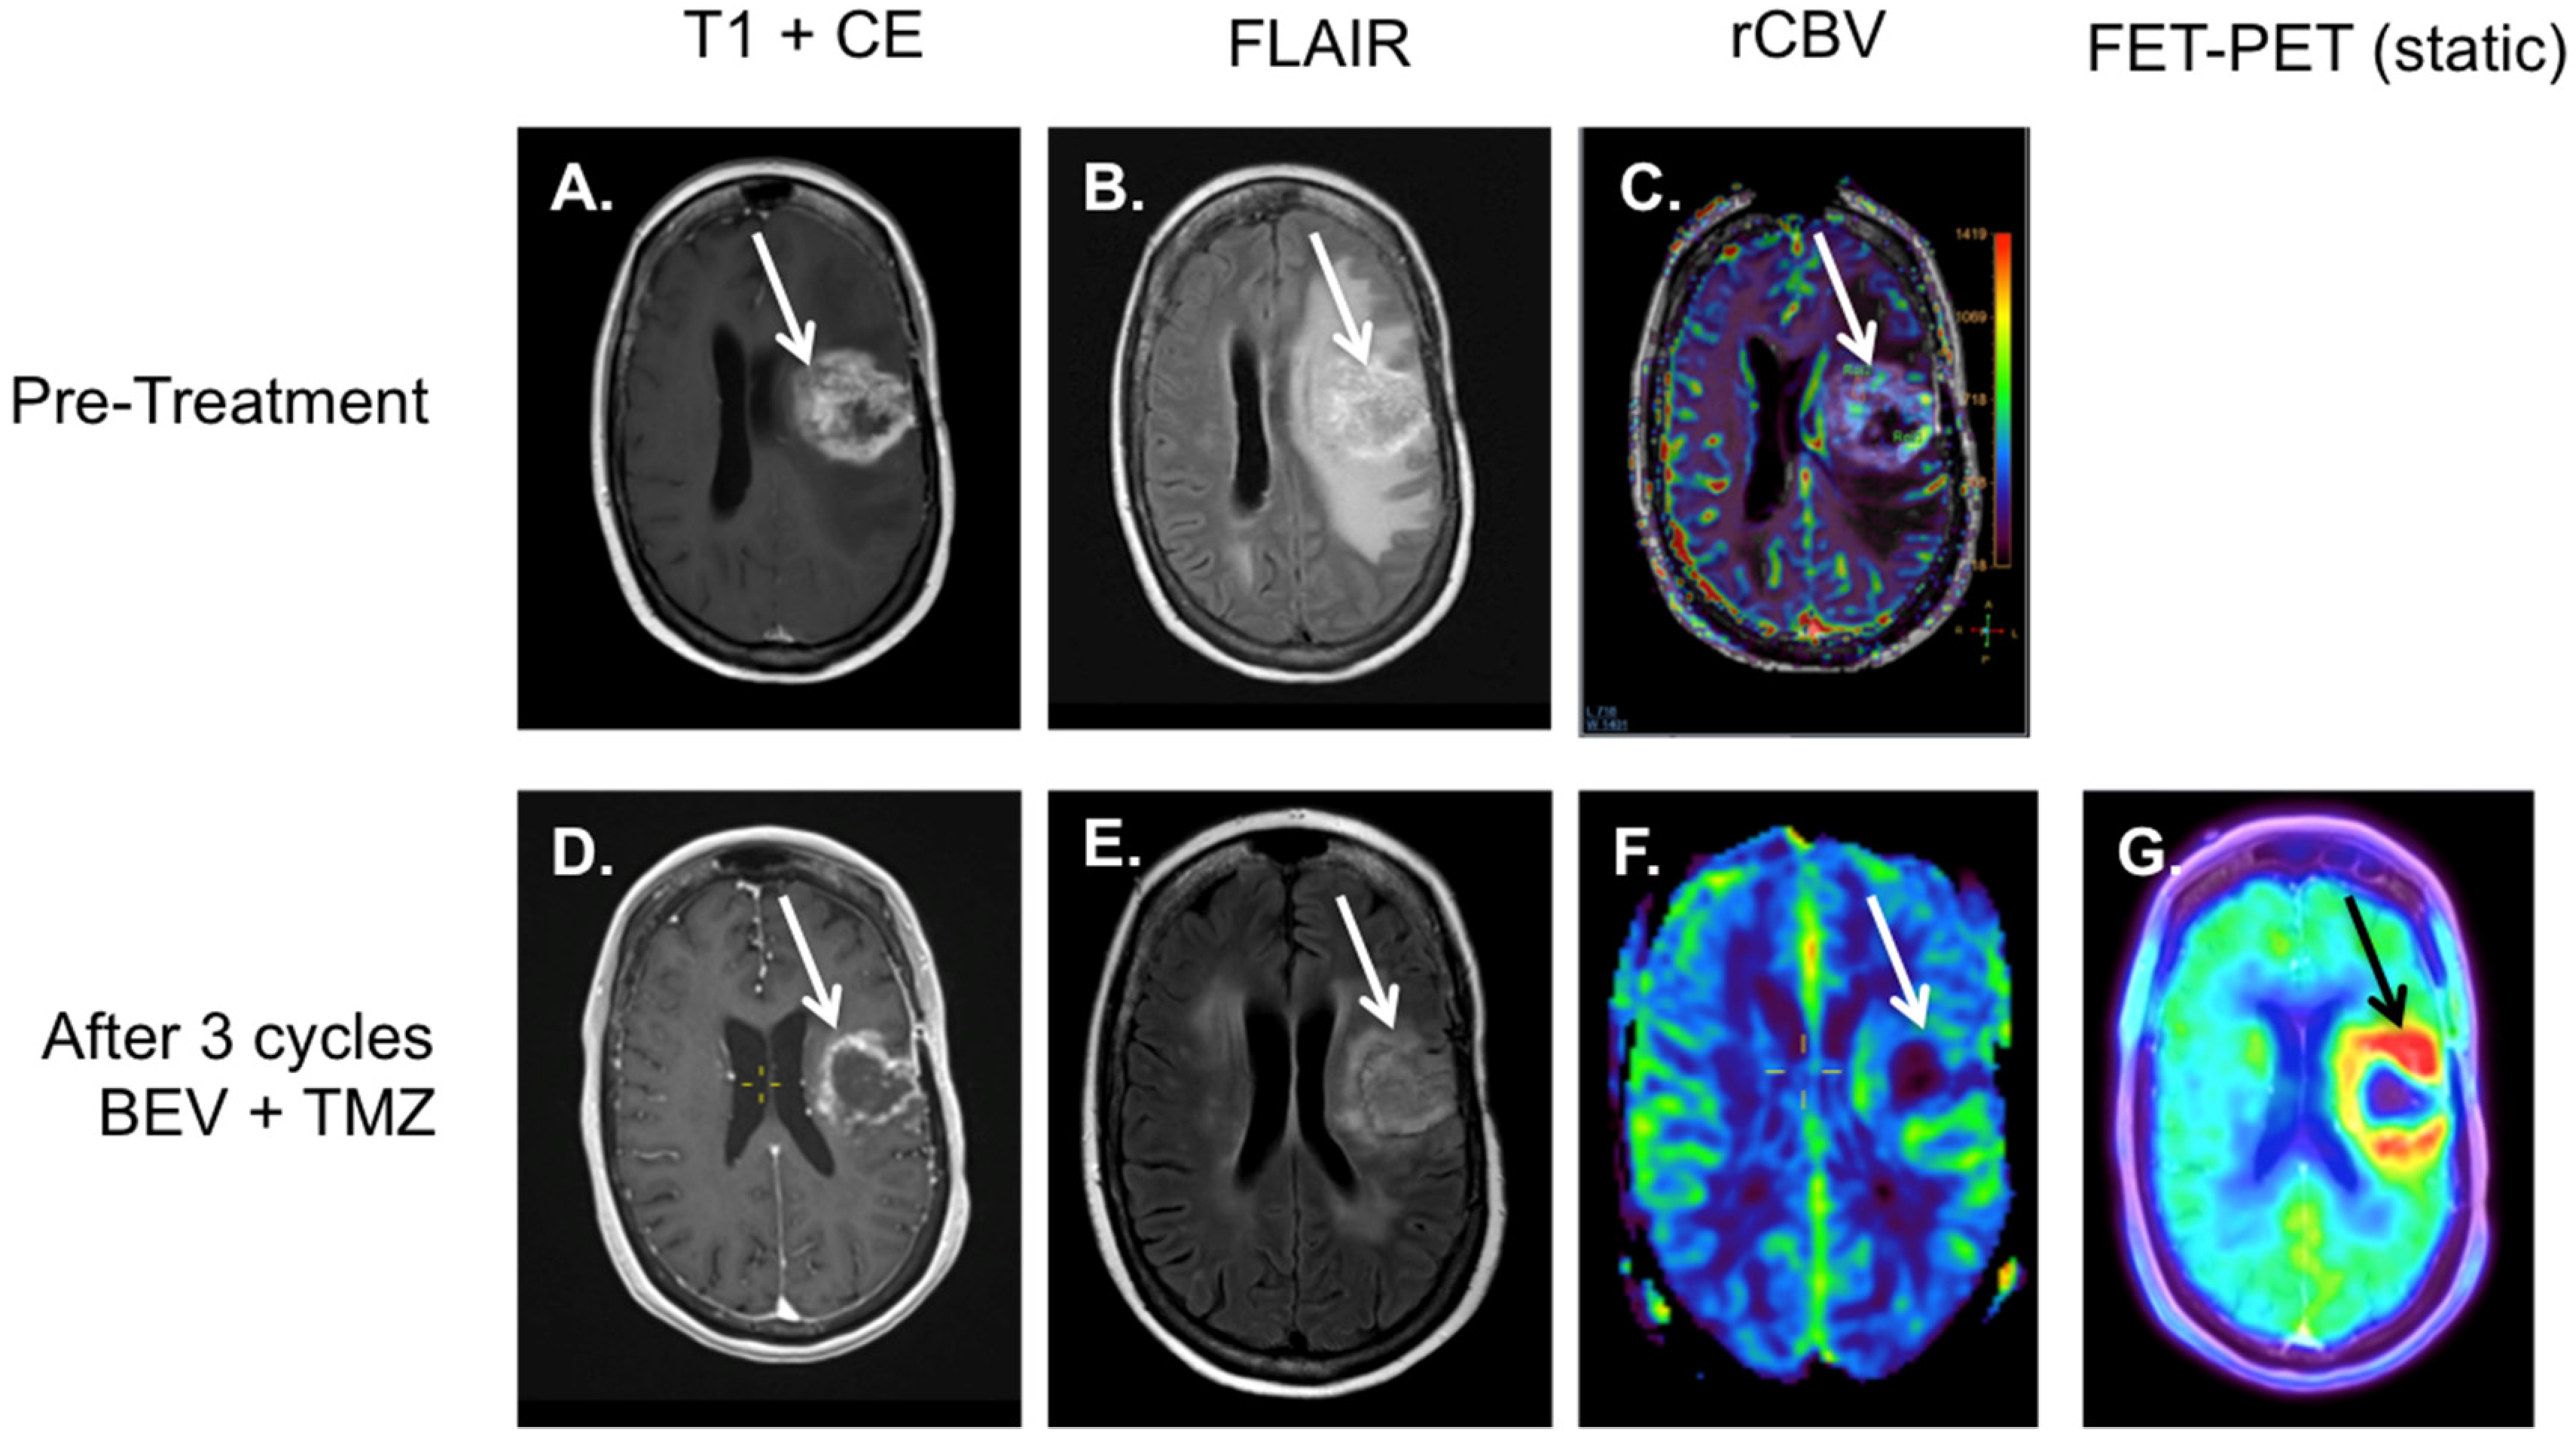

4. 18F-FET-PET-MRI